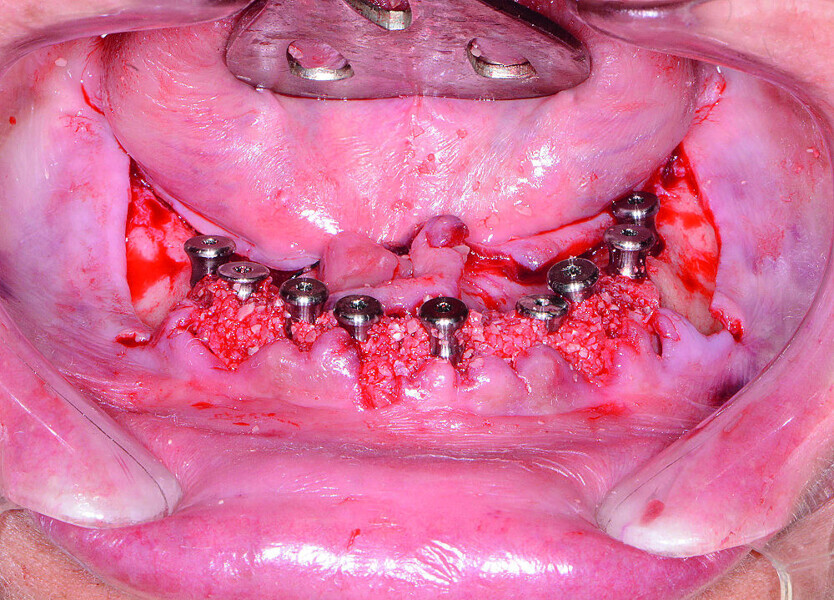

Fig 15 Implants et coiffes de cicatrisation entourés du matériel de greffe